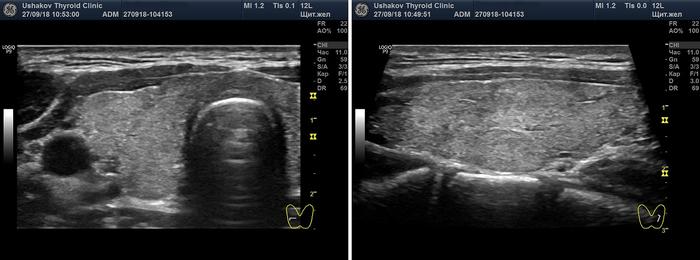

- Тиреоидит Хашимото: округлые контуры и неоднородная гипоэхогенная структура с выраженными фиброзными полосами в паренхиме при атрофической железе на последних стадиях болезни.

Общие патофизиологические и хирургические аспекты. Обычно диффузное и симметричное увеличение щитовидной железы. Масса: 50-150 г.

В начальной стадии хронического аутоиммунного тиреоидита наблюдается повышенное кровоснабжение, после чего оно постепенно снижается. В более поздних этапах фиксируется как нормальное кровообращение, так и пониженное. При остром и подостром тиреоидите расширение артерий указывает на активность воспалительного процесса, а по мере выздоровления скорость кровотока снижается.